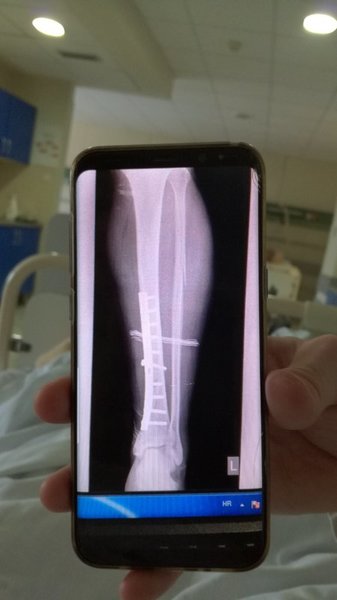

Sympatycy SlawoyAMD Opublikowano 8 Czerwca 2019 Autor Sympatycy Opublikowano 8 Czerwca 2019 Poskrecali kość... pękła na skos, gipsu nie ma... na razie boli potwornie, jakbym sie w piszczel walnął. Może za jakis czas znieczulenie zacznie działać. Jeszcze gorsze jest to, że leżę na jakim geriatyku i dziadki tu siorbia, mlaskaja, pierdza... TV na salach nie ma. Wiec nie idzie ich zagłuszyć...

darecki2059 Opublikowano 8 Czerwca 2019 Opublikowano 8 Czerwca 2019 No ładnie kulaska połamałeś. Dwie kości poszły. Śrubek też nie żałowali. Trzymaj się i teraz zamiast piwa trzeba będzie jogurty pić, żeby ładnie się zrosło.

Sympatycy SlawoyAMD Opublikowano 8 Czerwca 2019 Autor Sympatycy Opublikowano 8 Czerwca 2019 Gipsu nie mogą jeszcze założyć, bo musi zejść opuchlizna... Standadowa procedura. Na zdjęciu jeszcze zdrowy, a później fajna siostrzyczka w ambulansie... Ladnie śpiewała mi dla zabicia czasu w przelocie do Mostaru... 2